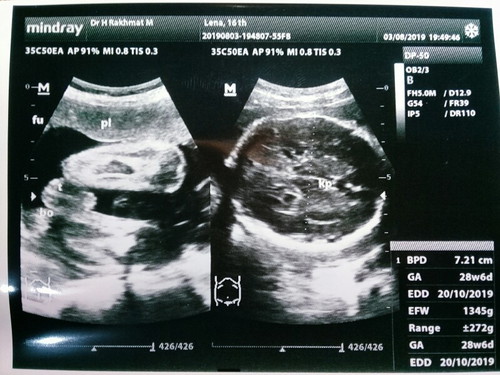

Bund wajar gak sih udah 29 minggu tapi berat janinnya baru 1345g? Apakah gak terlalu kekecilan bund?

Sama bun๐ช, kmaren pas 28w , normal ko bun kta bidan ๐คญ alhamdulillah nutrisi yg diserap baik jd dedekny sdkit lbih gede dr uk umumnya ๐คญ

Wajar bun, malah dlu sya 28w 1,3kg berat nya..

Masih normal bun saya pas 28w 1,2kg sekarang 33w 2,2kg

Nah apakabar. Saya bun waktu 28w beratnya 1000gr . Tapi pas 34w jadi 2396gr